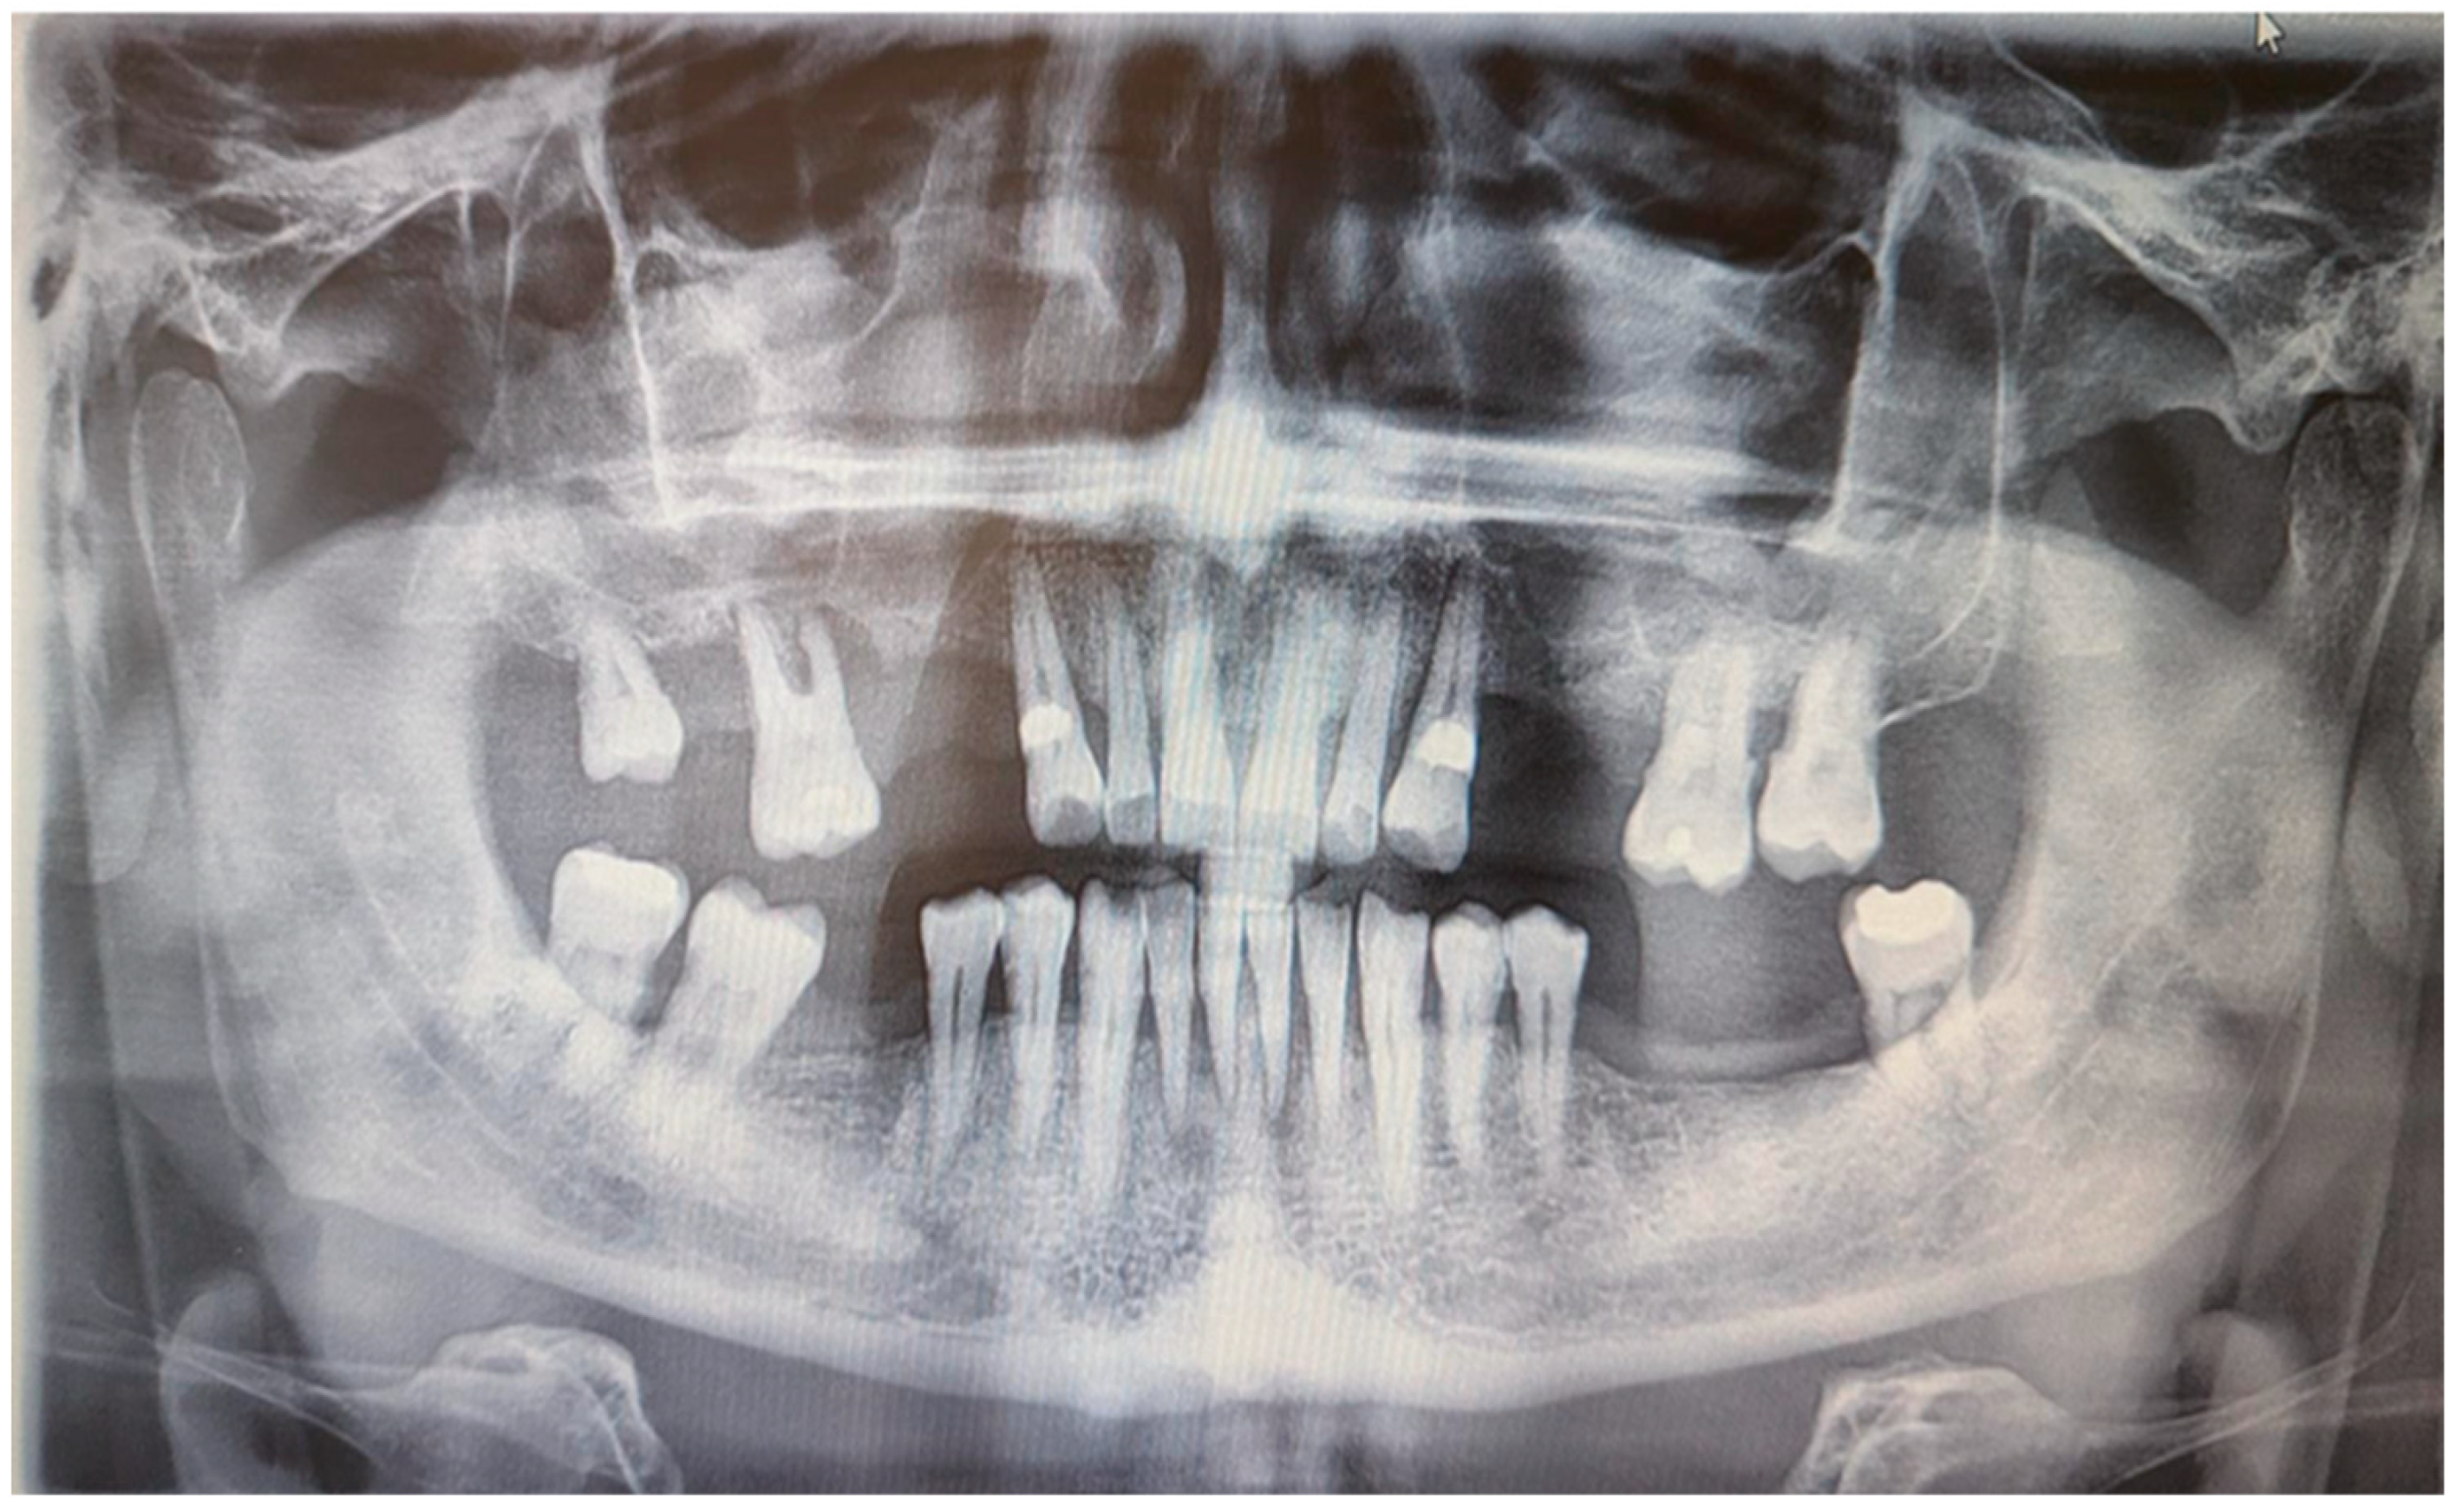

Skin prick tests for airborne and food allergies were negative, as were epidermal prick tests. Tuberculosis, sarcoidosis, and HBV and HCV infections were excluded. An abdominal ultrasound showed grade II fatty liver disease without liver enlargement. Chest X-ray was normal. A rheumatological consultation ruled out systemic connective tissue disease and other inflammatory musculoskeletal conditions, with an antinuclear antibody (ANA) titer of 1/80. A laryngological consultation found no signs of laryngological infection, and neurological examination revealed no peripheral facial nerve palsy. A dental examination conducted at the Department of Oral Surgery, Periodontal Diseases, and Oral Mucosal Diseases at Poznan University of Medical Sciences showed no signs of a fissured or plicated tongue. However, an intraoral examination revealed mild overgrowth of the gingival papillae and marginal gingiva. According to the Research Diagnostic Criteria for Temporomandibular Joint Disorders (RDC/TMD), there were no abnormalities in the temporomandibular joint or masticatory muscles, and no acoustic disturbances were detected in the temporomandibular joints. Additionally, there were no symptoms of stomatitis. Orthopantomographic examination showed significant bone loss around tooth 16 and less prominent bone loss in the lateral compartments of both maxilla and mandible. Moreover, the OPG showed discreet periapical radiolucency around mandibular incisors. There were no bone lesions. There were no defects of TMJ and maxillary sinus on both sides (Figure 2).

Figure 2. Digital OPG of the patient.

Medicina 61 00299 g002